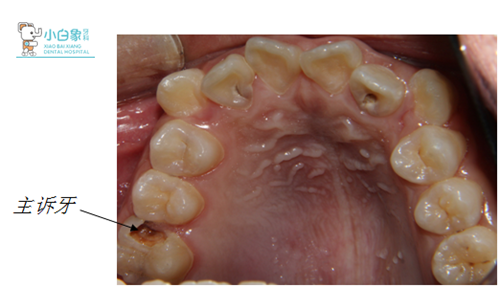

患者 :男 14岁

主诉:右上后牙疼痛10日余。

检查:颌面部查未见异常,口内查:牙列不齐,16近中临面龋坏达髓腔,近中缺损至龈下,探诊(-),温度测试无反应,叩(土),牙龈无红肿。36合面大面积缺损,髓腔暴漏,探诊(-),温度测试无反应,叩(+),牙龈无红肿。17,26,27,37,46,47合面龋坏达牙本质深层,探诊敏感,温度测试正常。14,24合面龋坏达牙本质浅层,探诊(-),温度测试正常。15,25,34,35,44,45萌出,窝沟较深,着色,无龋坏。12,22舌侧窝沟龋坏达牙本质深层,探诊敏感,温度测试正常。全口卫生差,软垢覆盖牙面二分之一,牙龈无红肿。

X线:16低密度影像达髓角